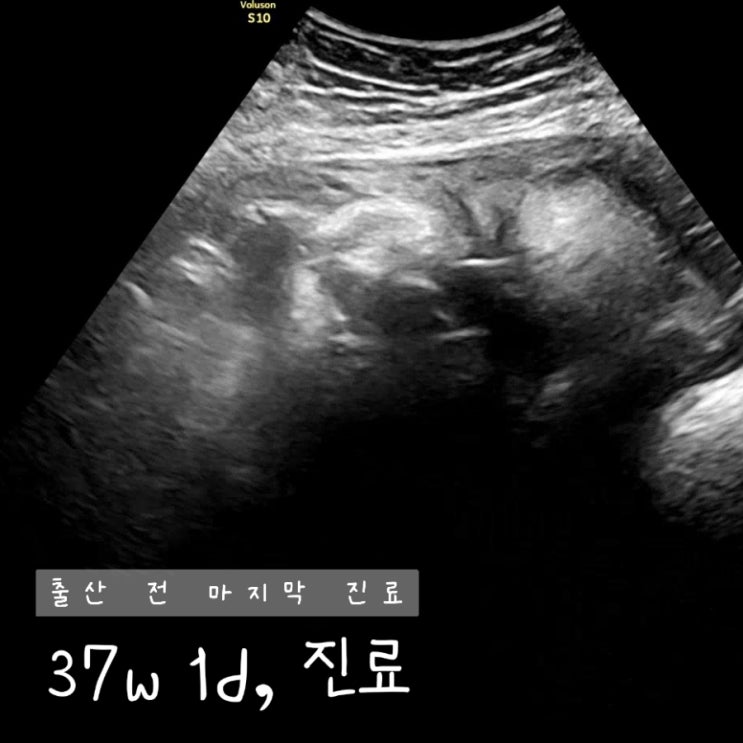

[37w] 37주 출산 전 마지막 진료, 원주 미래산부인과, 제왕절개, 수술 안내사항

안녕하세요. 열무 만나는 날 D-6 임테기 두 줄 본지 얼마 안 된 것 같은데 벌써 출산하는 날이 다가오고 ...